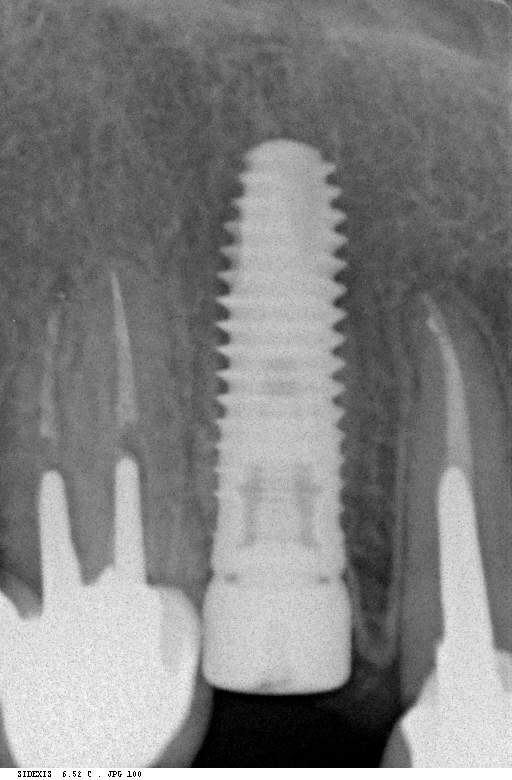

Рекомендации по установке имплантов. Для всех. Часть II.